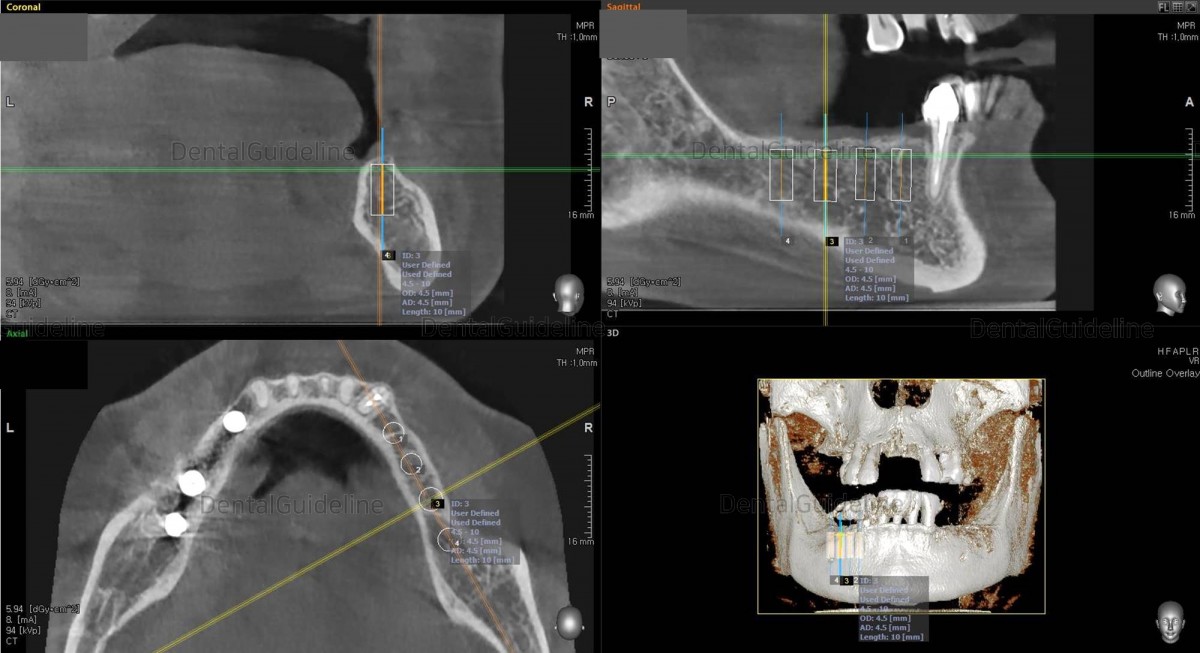

CBCT

scan. Arum NB-1 Ø4.0/L10

CBCT scan Arum NB-1 Ø4.5./ L10

(20Ncm) at

the 1st molar zone.